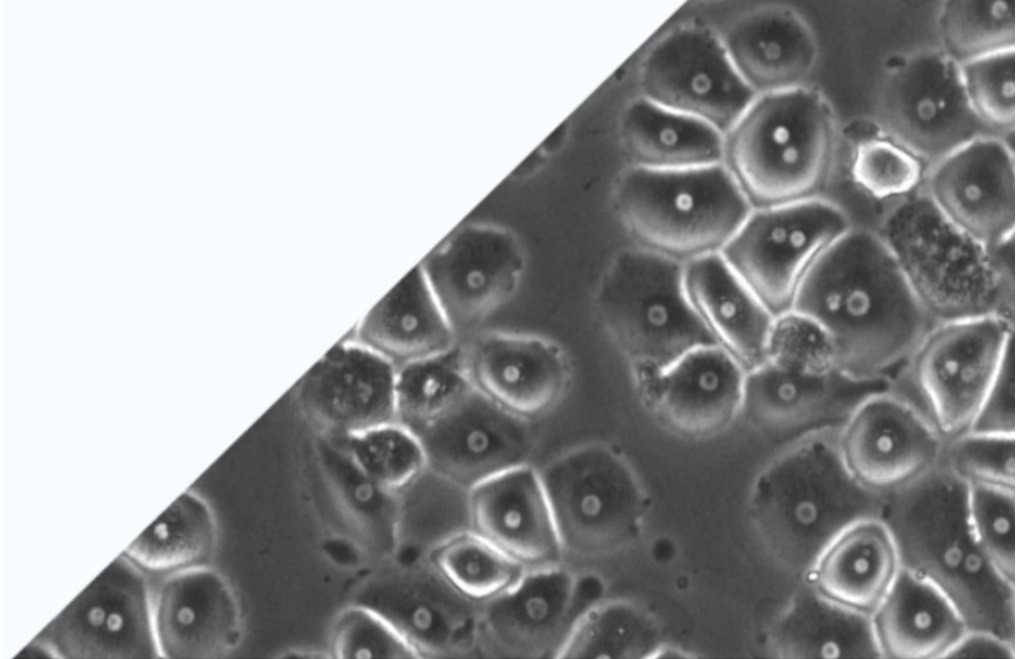

We partner with many GLP labs in Europe, China, USA providing human cells, and animal cells for the prediction of toxic and long-term effects of agents on the human body and the environment. Our cell culture systems are important for your day-to-day work. Human and non-human hepatocytes are available as fresh or cryopreserved.

Cell and Tissue Products

Liver products

Human liver cells

Animal liver cells